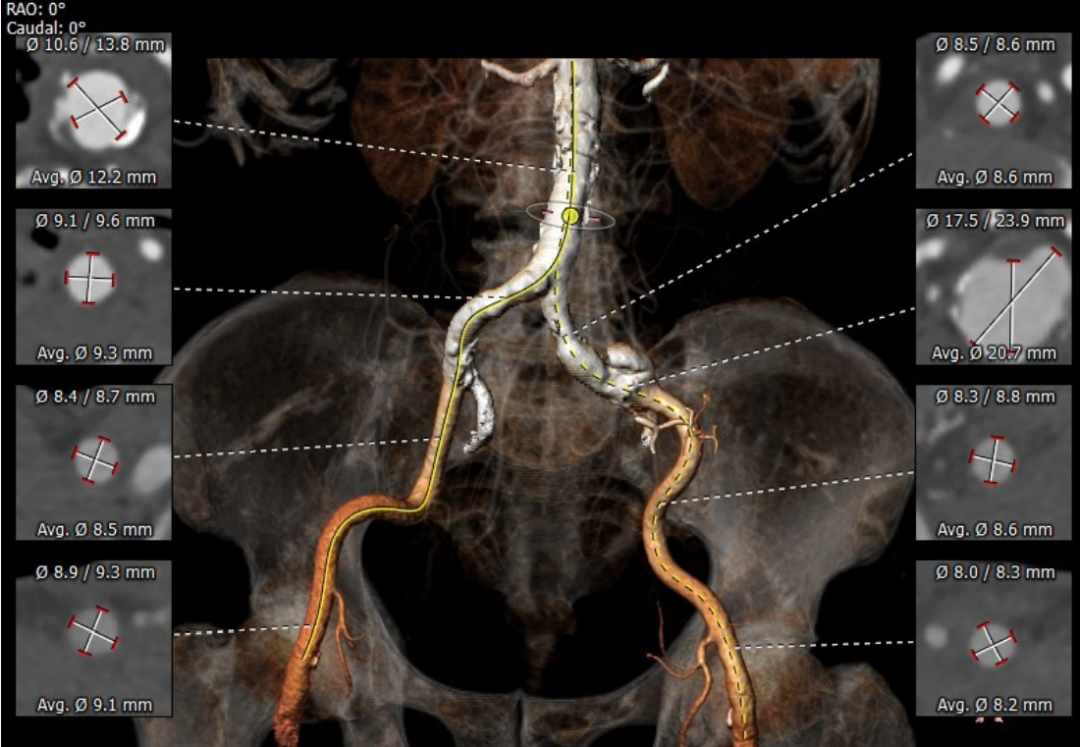

患者男性,78岁,术前心脏超声提示主动脉瓣重度狭窄伴轻度返流。CT评估结果显示三叶瓣,钙化均匀分布在三冠瓣,瓣环平均直径26.8mm,面积径25.7mm,左、右冠脉开口高度较高,无冠脉梗阻风险。下肢血管评估发现患者左侧髂外动脉瘤,下肢血管轻微钙化。

主动脉瓣环

三叶瓣

左冠开口高度

右冠开口高度